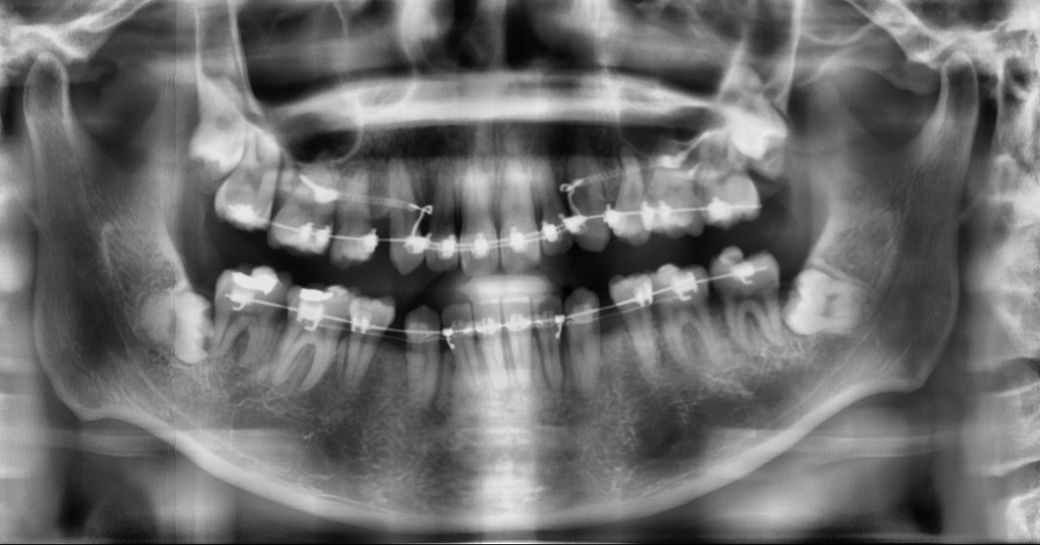

현재 교정치료중입니다 (콤비)

파노라마는 얼마전 사랑니 발치전후에 찍은 사진으로 한달간격으로 찍었습니다. 몇달전부터 오른쪽 어금니(파노라마상 왼쪽 어금니)가 씹을때마다 불편했는데 파노라마를 찍어보니 다른 부분이랑 조금 다르게 조금 큰 까만 세로 선이 보여서 혹시 제가 씹을때 불편한것과 관련이있을까 싶어 여쭤봅니다. 왜 이럴까요..?

다른치료로 다른 치과에 방문했을때 저것이 치주인대부분이다. 저렇게찍힐수있다라는 말만 하시긴하셨어요.

교정치료중 생길수있는 증상이라 시간이 지나면 괜찮아질지...아니면 다른치료가 필요한 상황인지 궁금합니다

• 1번 째 사진